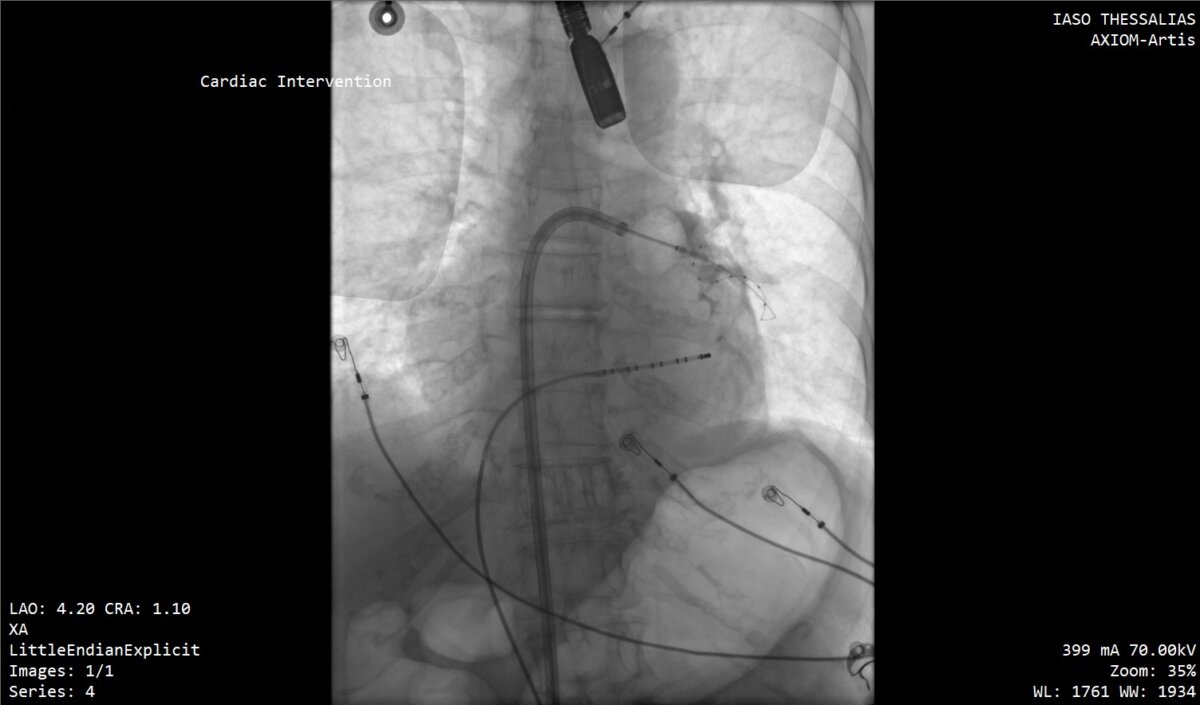

Στις συγκεκριμένες επεμβάσεις εφαρμόστηκε η σύγχρονη τεχνική κρυοκατάλυσης με τη χρήση ειδικού μπαλονιού κρυοπηξίας (Cryoballoon), το οποίο επιτρέπει την ελεγχόμενη ψύξη («πάγωμα») του καρδιακού ιστού γύρω από τις πνευμονικές φλέβες, επιτυγχάνοντας με ασφάλεια και ακρίβεια την ηλεκτρική τους απομόνωση. Η μέθοδος χαρακτηρίζεται από υψηλά ποσοστά επιτυχίας, μειωμένο χρόνο επέμβασης και ταχεία ανάρρωση των ασθενών.